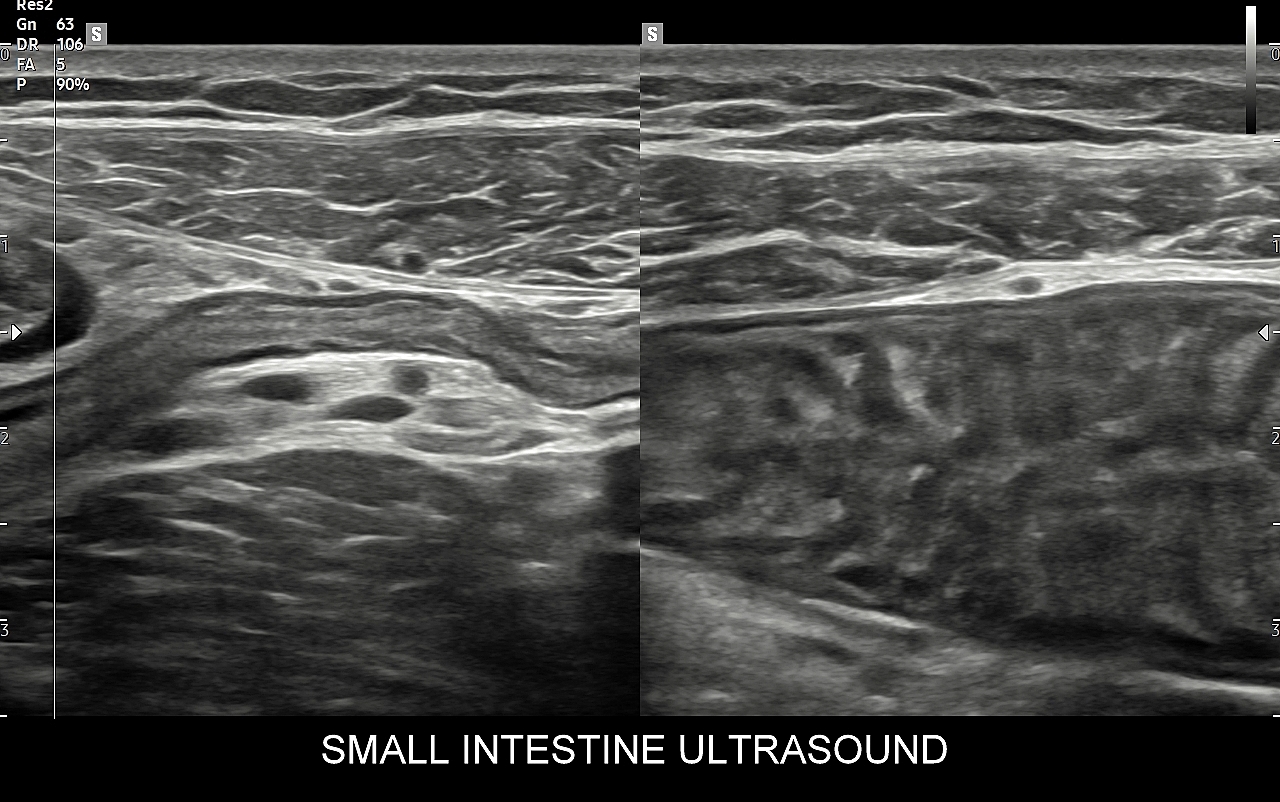

Klasyczne badanie USG jamy brzusznej obejmuje ocenę obrazową narządów wewnętrznych i struktur obszaru brzucha takich jak wątroba, pęcherzyk żółciowy i drogi żółciowe, trzustka, śledziona, nerki, pęcherz i drogi moczowe, gruczoł krokowy, macica, jajniki, przewód pokarmowy, wewnątrzbrzuszne węzły chłonne, przestrzeń zaotrzewnowa oraz naczynia jamy brzusznej. Badanie to jest podstawowym elementem procesów diagnostycznych w różnorodnych dziedzinach medycyny takich jak gastrologia, hepatologia, hematologia, endokrynologia, nefrologia, angiologia, chirurgia, urologia, czy ginekologia.

Badanie multiparametryczne MPUS jamy brzusznej